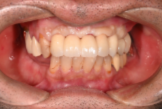

オールオン4の症例紹介②

Before

After

主訴

歯を入れたい

治療内容

上顎、下顎に対するインプラント治療を行った。

治療費

4,092,000円(税込)

治療期間

1か月

通院回数

3回

※治療回数は1回

想定されたリスク

※最終的な歯が入るまでは仮歯で過ごす必要がありました。

オールオン4は、少ないインプラント本数で多くの歯を補う治療法です。手術当日に仮歯を入れ、見た目と噛む機能をすぐに回復できます。